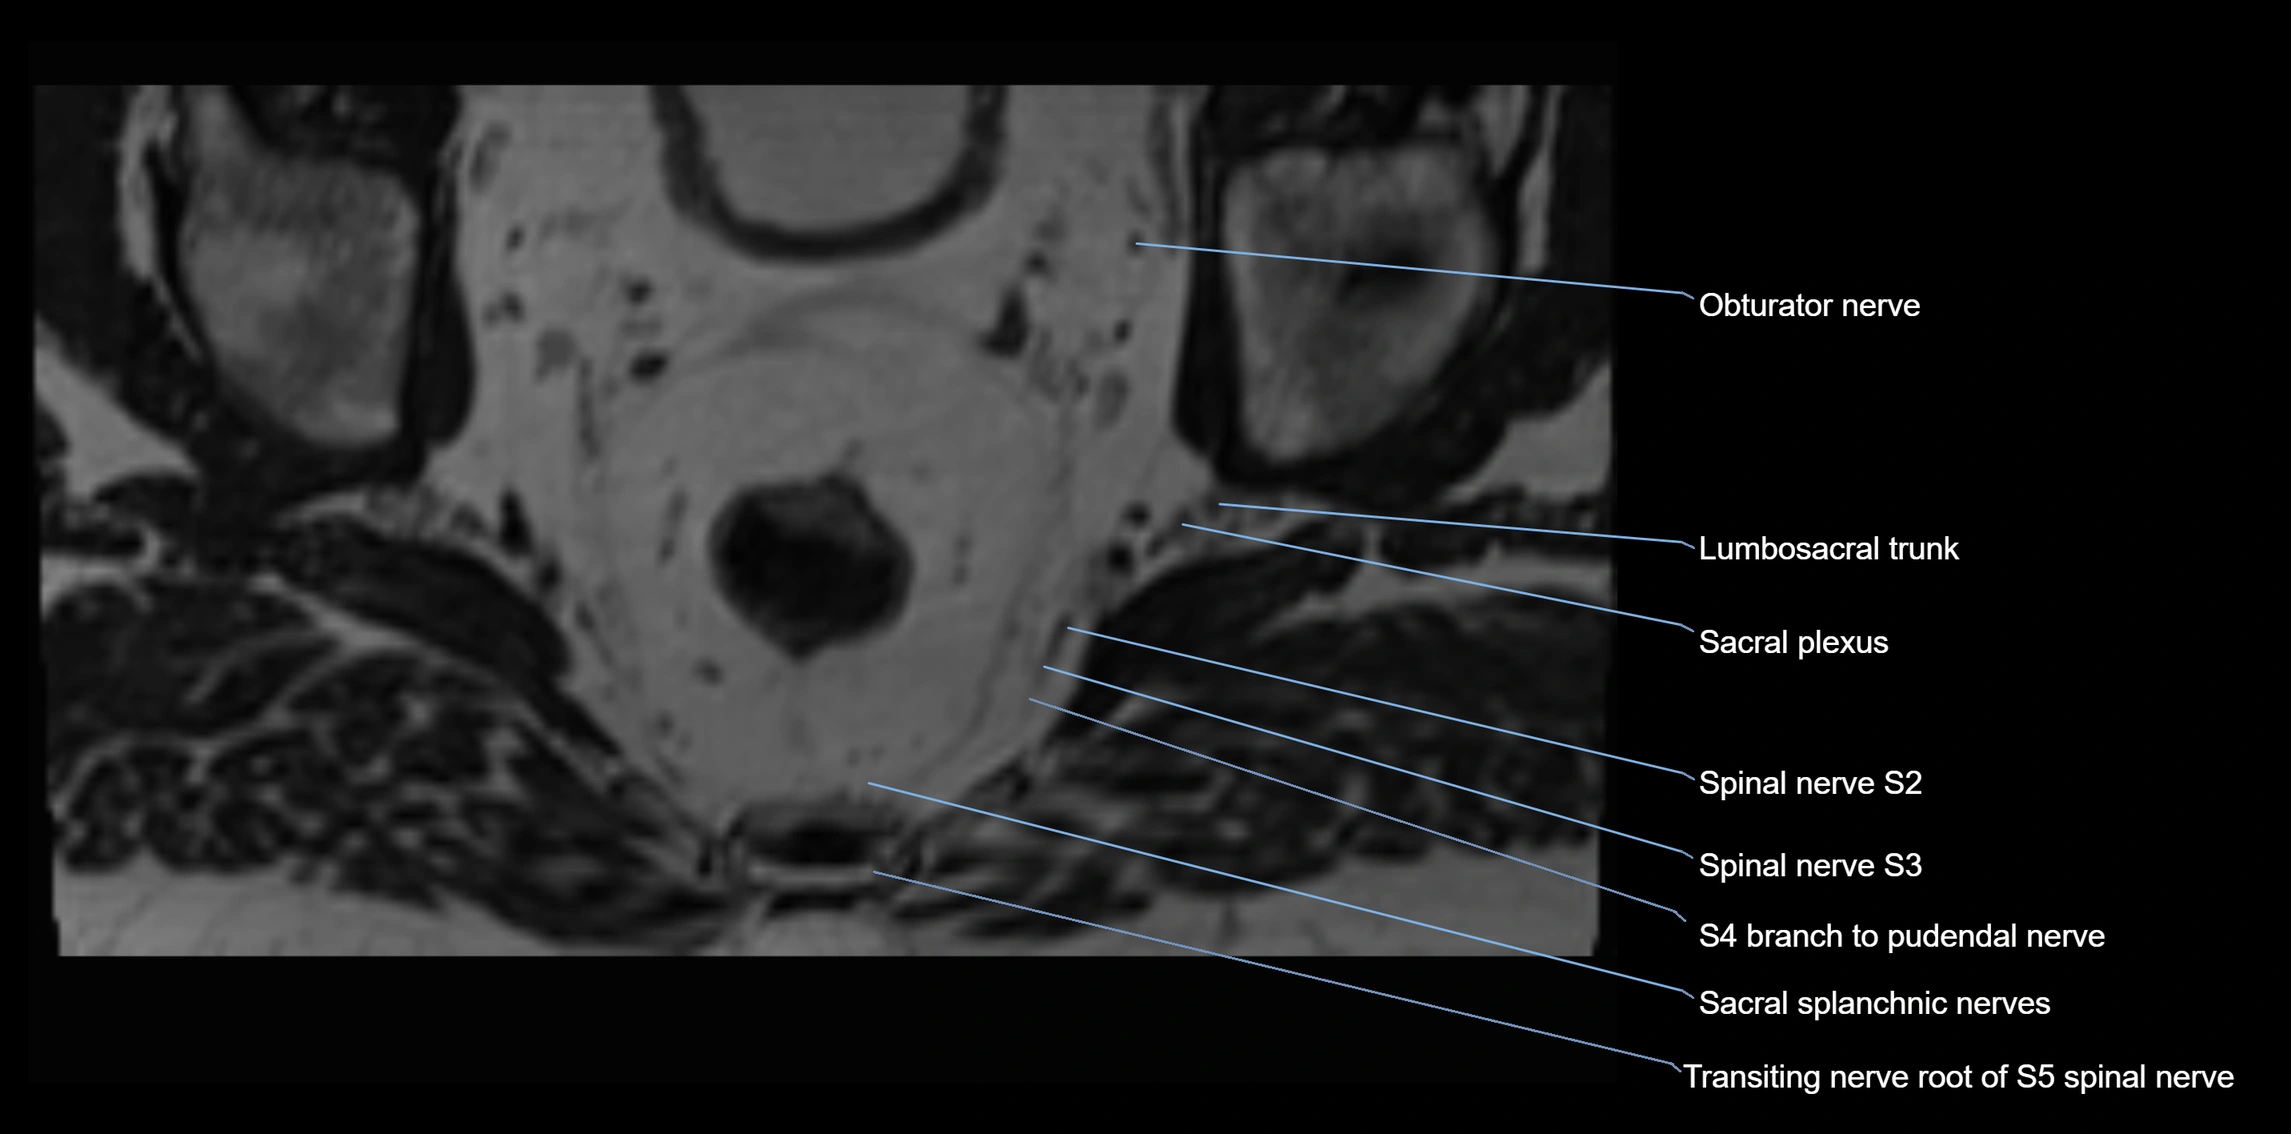

MRI Appearance

T1-weighted images:

• Nerve appears as a very thin low-to-intermediate signal intensity structure

• Surrounded by bright fat, aiding visualization

T2-weighted images:

• Nerve shows intermediate to mildly hyperintense signal compared to muscle

• Pathological involvement appears brighter

STIR (Short Tau Inversion Recovery):

• Normal nerve appears dark

• Inflamed or entrapped nerve appears bright hyperintense

T1 Fat-Sat Post-Contrast:

• Normal nerve enhances minimally

• Pathologic nerve (neuritis, entrapment, tumor infiltration) shows focal or diffuse enhancement

3D T2 SPACE / CISS:

• Nerve appears intermediate to mildly hyperintense compared to muscle

• Surrounded by bright fat or CSF, improving visualization

• Best sequence for mapping small pelvic nerves such as the anococcygeal